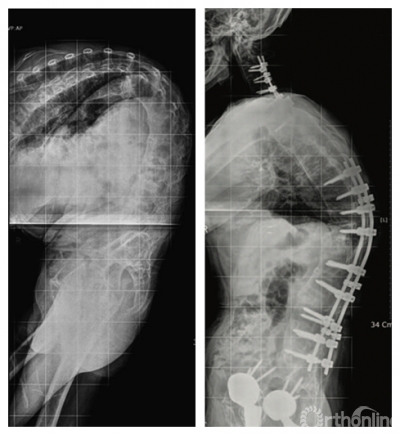

颈椎截骨是治疗颈胸段后凸畸形的有效技术,其适应证:包括重度颈胸段后凸畸形致平视功能受限、脊柱后凸畸形经胸腰椎截骨术后平视功能仍受限及颈胸段近端交界性后凸畸形需再次手术。

2.2.2 C7 经椎弓根闭合楔形截骨( C7 pedicle subtraction osteotomy, C7 PSO )

C7 PSO的优点在于生物力学稳定性强,前方组织撕裂性损伤和截骨椎脱位可能性降低,神经并发症发生率较C7-T1伸展性截骨低。适用于前纵韧带严重骨化及复杂双平面颈胸段畸形患者。手术时后路暴露截骨椎上下至少三个椎体,颈胸椎预固定后完全切除C7椎板、C6椎板下半及T1椎板上半部分,临时固定一侧,另一侧去除截骨椎内大部分松质骨,并将椎体后壁推向椎体去除松质骨后形成的腔室内并保持截骨前壁的连续性。一侧固定后同法处理对侧。椎体两侧截骨完成后,上抬患者头部造成C7压缩骨折以矫正后凸畸形。对于合并侧凸畸形者则采用不对称截骨。

单纯颈胸段和胸腰段后凸畸形可分别行颈胸段、胸腰段截骨矫正,整体后凸畸形则要考虑截骨顺序。Koller 等认为若患者有重度颈椎及轻中度胸腰椎后凸畸形可先行颈椎截骨术,术后根据患者特点决定是否行进一步腰椎截骨。Kim等认为在患者脊柱极重度后凸畸形(chin-on-pubis )时,可按颈椎、胸椎和腰椎顺序依次截骨。